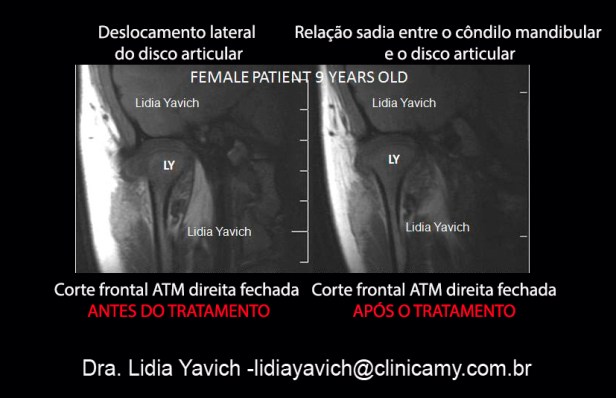

4) Para provar que temos recapturado o disco articular, precisamos da comparação da RNM antes e após o tratamento. O objetivo de este post é a comparação das imagens, para isso escolhi imagens expressivas. E simplesmente para comparar os cambios nos tecidos moles e nos tecidos duros.

Comparação de cortes das RNM antes e após o tratamento em casos de Patologias da ATM em crianças e adolescentes.

Patologias da ATM, diagnóstico diferencial no tratamento de crianças e adolescentes. Paciente de sexo feminino. 9 anos de idade. Queixas principais: Dor no ouvido direito, dor de cabeça principalmente no lado direito. Dor na parte posterior do pescoço, principalmente no lado direito.

Dor nos ombros principalmente no lado direito. Dor na ATM, mais do lado direito. Dor na mastigação. Sensação de ouvido entupido. Dor na abertura e fechamento da boca. Ela caiu na piscina e bateu o queixo, Começo a sentir sintomatologia só quatro meses após a queda; inicialmente a dor era no começo da noite, posteriormente era continua.

Antes de vir no consultório tinha sido medicada por vários colegas com Anti-inflamatórios e analgésicos que já não funcionavam. As imagens solicitadas pelos colegas com panorâmica e TC não mostravam informação relevante. Inclusive os cortes sagitais da RNM, não revelam informação relevante NESTE CASO SÓ O CORTE FRONTAL nos mostra o deslocamento. Realinhamento mandibular com a técnica neuromuscular fisiológica. Paciente hoje em dia assintomática.